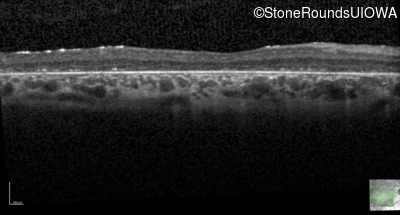

Age at visit: 6 years

OD OS

Age at visit: 5 years

Age at visit: 7 years

Age at visit: 8 years

Age at visit: 9 years

Age at visit: 11 years

Age at visit: 12 years

Age at visit: 13 years

Age at visit: 14 years

Age at visit: 17 years